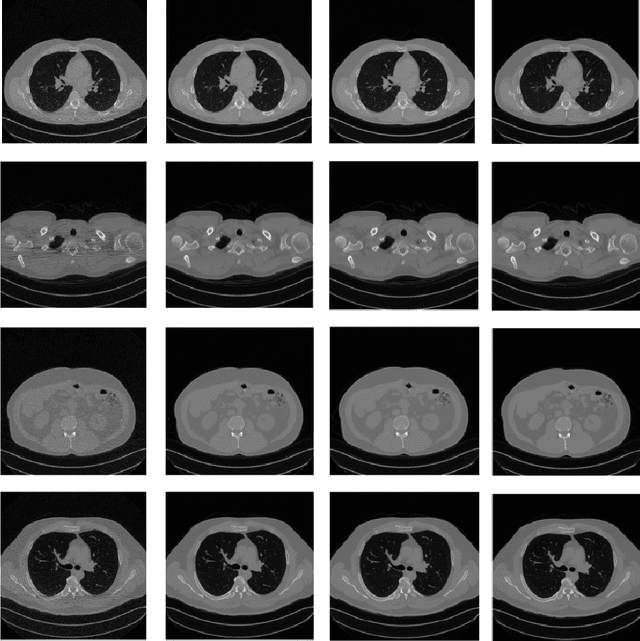

Abstract:Low-dose CT (LDCT) protocols reduce radiation exposure but increase image noise, compromising diagnostic confidence. Diffusion-based generative models have shown promise for LDCT denoising by learning image priors and performing iterative refinement. In this work, we introduce AST-n, an accelerated inference framework that initiates reverse diffusion from intermediate noise levels, and integrate high-order ODE solvers within conditioned models to further reduce sampling steps. We evaluate two acceleration paradigms--AST-n sampling and standard scheduling with high-order solvers -- on the Low Dose CT Grand Challenge dataset, covering head, abdominal, and chest scans at 10-25 % of standard dose. Conditioned models using only 25 steps (AST-25) achieve peak signal-to-noise ratio (PSNR) above 38 dB and structural similarity index (SSIM) above 0.95, closely matching standard baselines while cutting inference time from ~16 seg to under 1 seg per slice. Unconditional sampling suffers substantial quality loss, underscoring the necessity of conditioning. We also assess DDIM inversion, which yields marginal PSNR gains at the cost of doubling inference time, limiting its clinical practicality. Our results demonstrate that AST-n with high-order samplers enables rapid LDCT reconstruction without significant loss of image fidelity, advancing the feasibility of diffusion-based methods in clinical workflows.